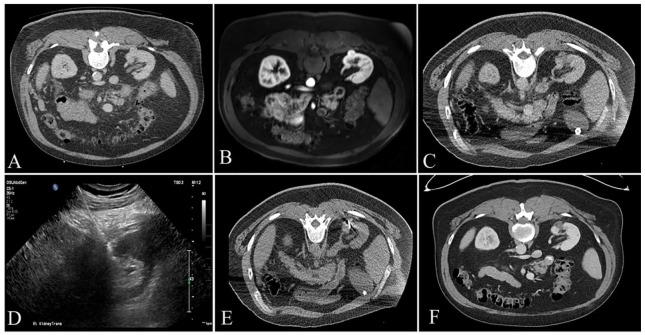

Abstract Image